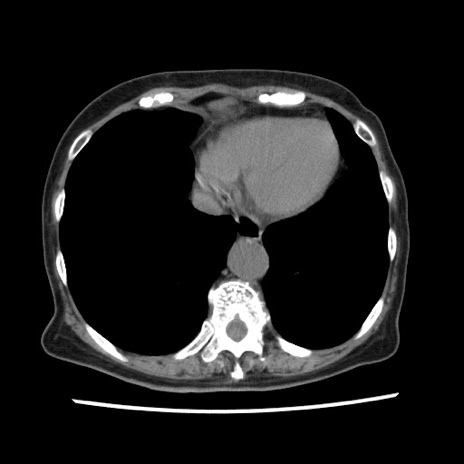

症例1(横断像)

【症例】80歳代女性

【主訴】腹痛

【現病歴】8時間前から腹痛あり来院。

【既往歴】糖尿病、脂質異常症、子宮体癌にて子宮全摘術

【身体所見】意識清明・会話良好だが腹痛で苦悶様、全腹部にわたって反跳痛と圧痛あり

【データ】WBC 13600、CRP 0.14、LDH 224、CK 90